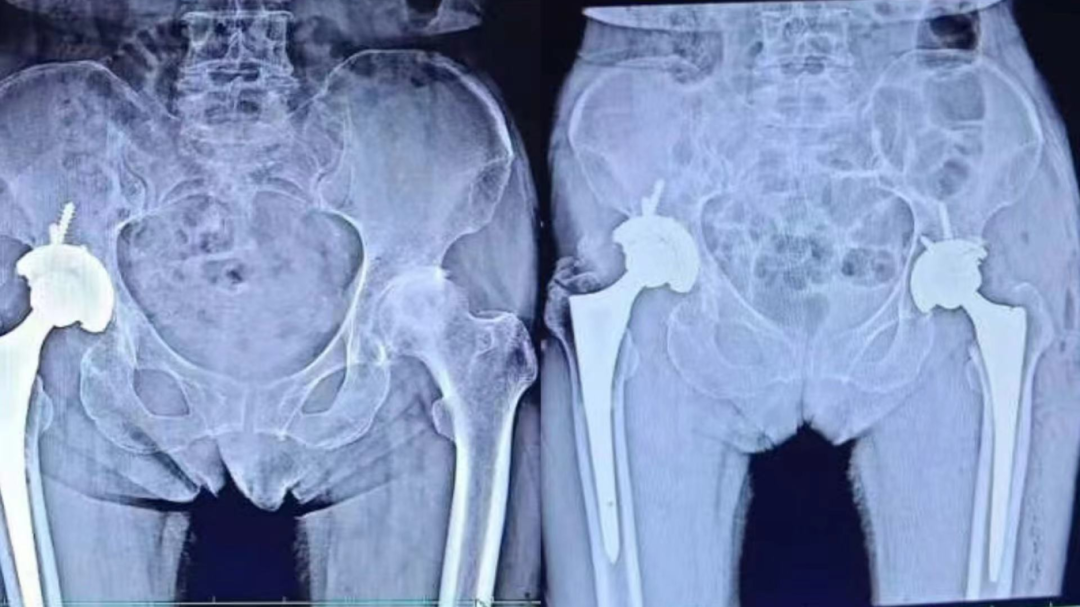

双侧股骨头坏死行髋关节置换术

髋关节置换术后假体松动行关节翻修术